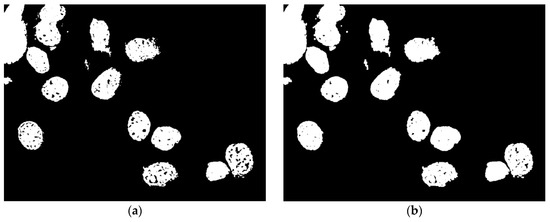

After grayscale conversion, segmentation is made with automatic threshold to separate cells, as shown in Figure 7. To improve image quality and correct any defects due to Otsu’s binarization, such as holes in cell nuclei, the process benefits from the use of aperture in combination with dilation.

Figure 7. Output images of Otsu’s binarization (a) and morphological operations (b).